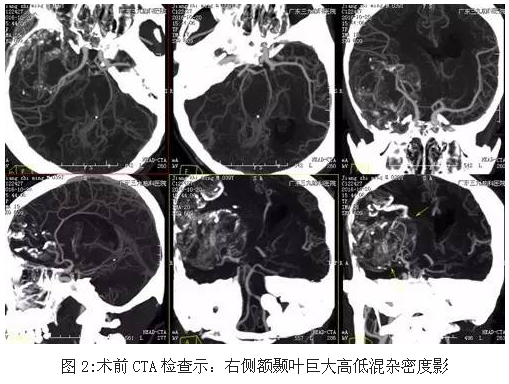

患者江某某,男性,39岁,发热后头部胀痛,当地医院就诊,CT显示:颅内巨大占位性病变,为求有效治疗,来我院就诊。入院后完善术前相关检查,术前CT显示大片状、点状钙化高密度影,术前CTA检查示:右侧额颞叶巨大高低混杂密度影,术前磁共振显示肿瘤位置及大小约10.8×8.6×8.7cm,完善术前准备后,行全麻下右侧额颞岛叶-基底节肿瘤切除术,手术由神经外一科主任张良主刀完成,术中肿瘤全切,术后恢复良好。

少突胶质细胞瘤无包膜,与周围脑组织界限清晰,50%-80%%病例出现钙化,可散在或融合成较大的钙化小体,弯曲条带状钙化为其特征性表现,但广泛钙化罕见。本例肿瘤巨大(范围约为10.8×8.6×8.7cm),CT示斑片状低密度影及条带状典型高密度钙化影,病灶内及边缘示多发迂曲血管影沿钙化斑块走行,强化后呈轻度不均匀异常强化影,均符合少突胶质瘤典型影像学改变。